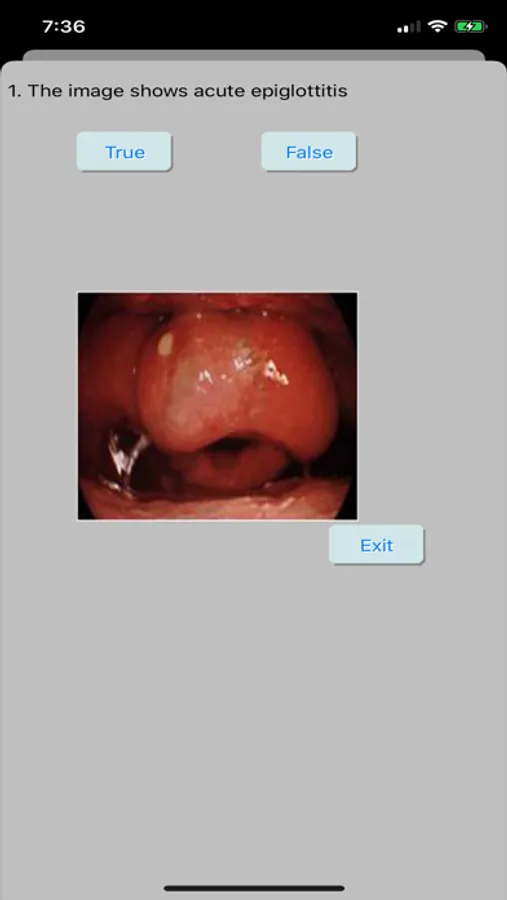

Anesthesia 101 Screenshots